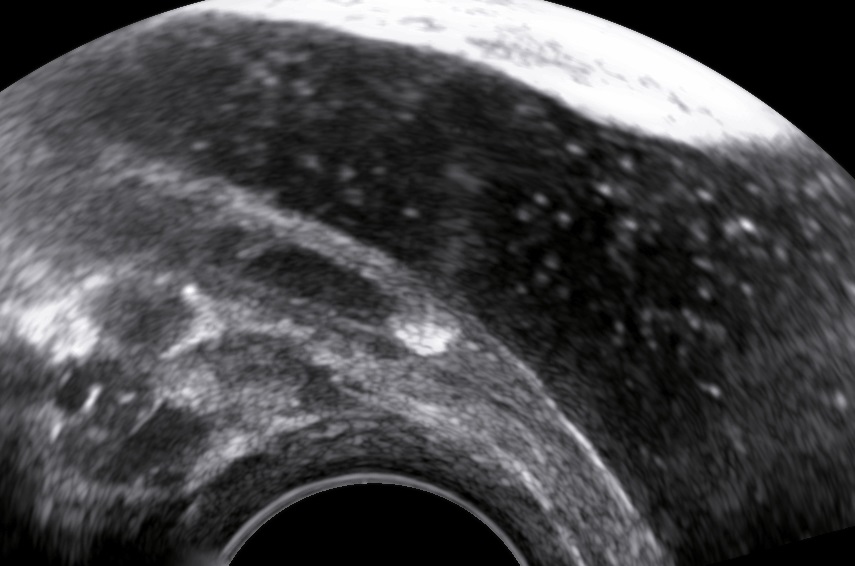

The abdominal ultrasound examination began with an intact pregnancy and a mild maternal hydronephrosis on the right side. The transvaginal sonography showed a distal ureteral calculus with dilatation of the right distal ureter.

The ureteric stone is perfectly visible with transvaginal sonography.